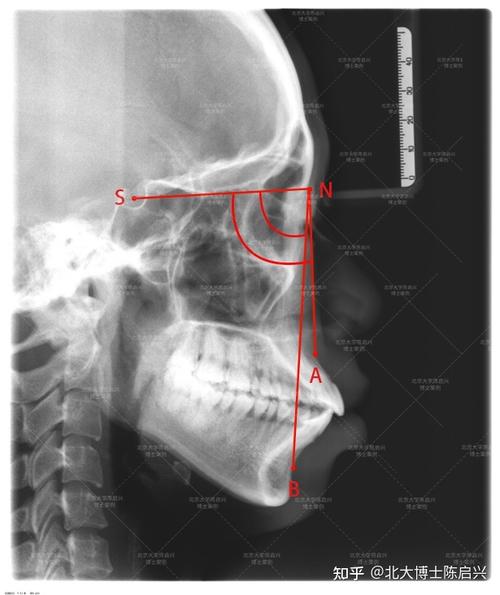

- A点(Subspinale,上齿槽座点):上颌骨前壁与梨状孔下缘的交点,位于上颌骨最前端,反映上颌基骨的位置。

- N点(Nasion,鼻根点):鼻额缝的最前点,位于颅底与前颅底的交界处,作为颅部的参考点。

- B点(Supramentale,下齿槽座点):下颌骨前颏联合部与下齿槽缘的交点,位于下颌骨最前端,反映下颌基骨的位置。

- 在X线片上精确标记A、N、B三点:N点通常位于鼻梁根部凹陷处;A点为上颌牙槽突最前点,与上颌中切牙牙根尖接近;B点为下颌牙槽突最前点,与下颌中切牙牙根尖接近。

- 连接N-A线(鼻根点至上齿槽座点的连线)和N-B线(鼻根点至下齿槽座点的连线),两条线在N点形成夹角,即为anb角。